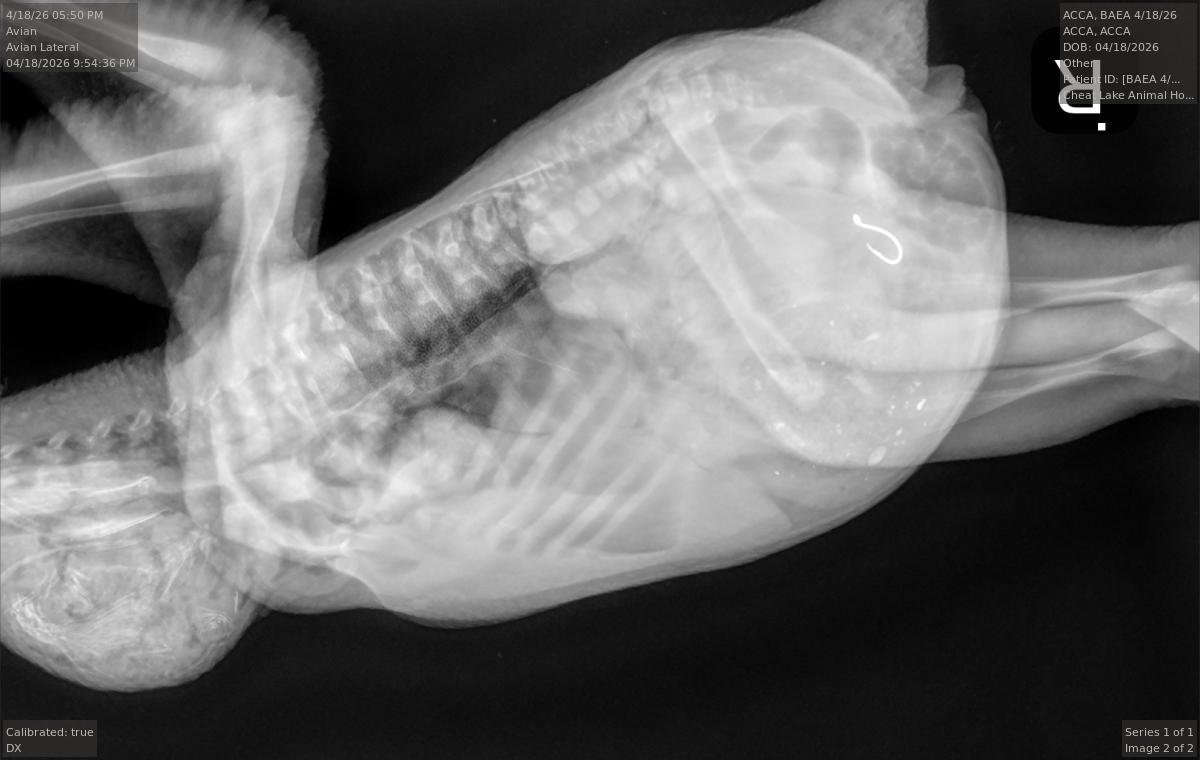

They first tried using endoscopy – a camera on a scope – but there was too much food in the bird’s stomach to be able to see the hook.

So they turned to surgery. His veterinary technician Cayce Dakon handled the anesthesia while Tricia Mayle was his surgical assistant.

He made an abdominal incision and removed the hook, which was still attached to the synthetic worm lure and the fishing line. USS11 was out of surgery around 8 p.m., he said.